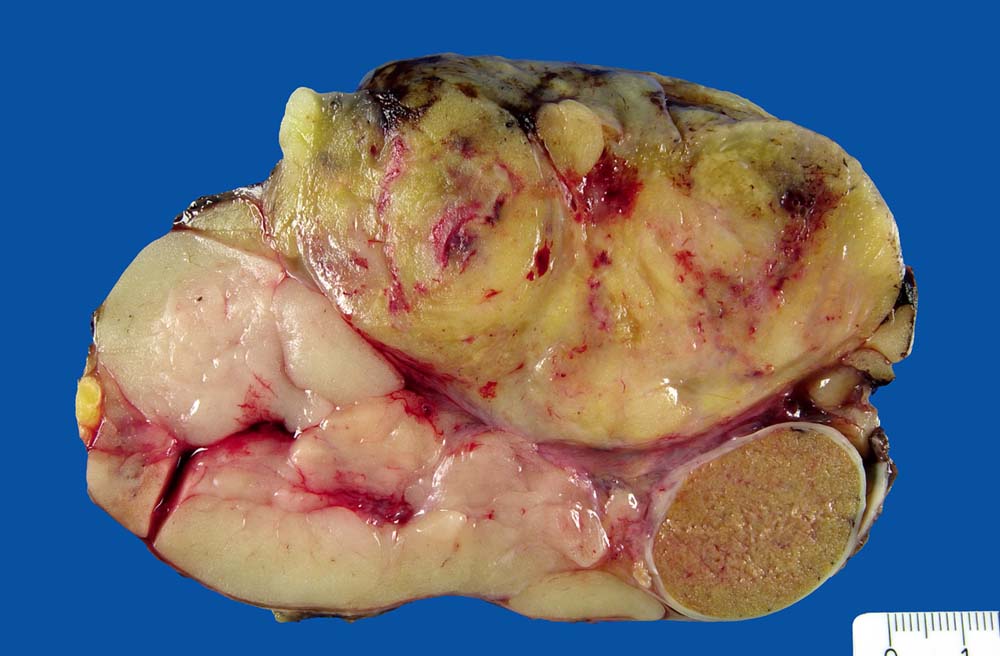

PathoPic ID 9174 - Hoch differenziertes Liposarkom

Hoch differenziertes Liposarkom

Der tumorfreie Hoden wird umgeben von teils fettähnlichem, teils fleischig weisslichem Tumorgewebe.

Gut differenziertes Liposarkom der peritestikulären Weichteile ohne Nekrosen. FNCLCC=1+0+1=2, maximaler Tumordurchmesser 11cm.

Hodentumor rechts.